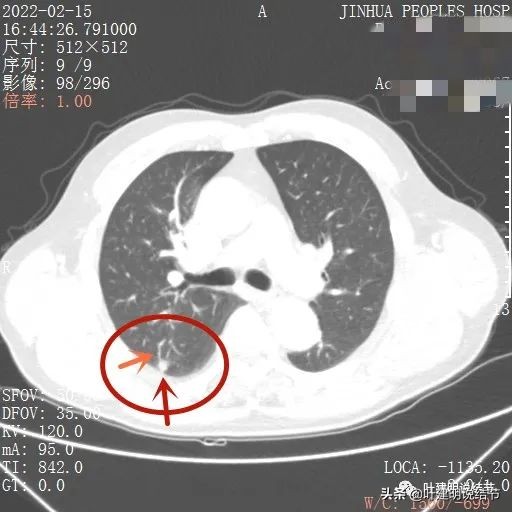

我们先来看下他的CT平扫5毫米层厚的图像:

病灶出现,有血管进入(桔色箭头),有轻微胸膜牵拉(蓝色箭头)

病灶基本实性,但边缘稍不平整,有的边比较平直,但仍是不光滑的